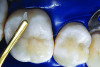

Figure 8. AND Figure 9. After the preparations were cleaned with 2% chlorhexidine, a selective etching of the cavosurface enamel was performed with 37.5% phosphoric acid gel for 10 seconds, rinsed for 5 seconds, and gently air dried. Notice the selective etch pattern of the enamel demonstrating a frosty appearance.

Figure 8

Figure 9